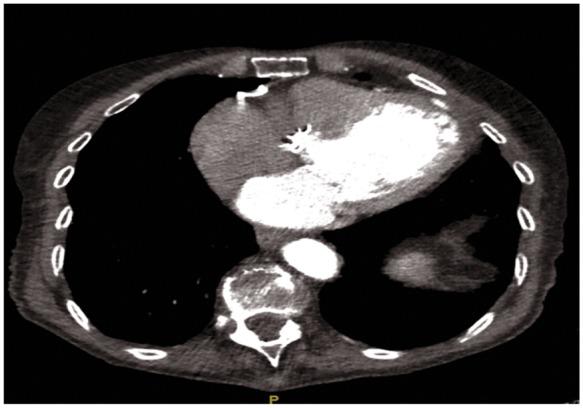

We report an 87-year-old woman treated successfully with 23 mm Sapien 3 transapical transcatheter aortic valve implantation for severe AS. She presented 4 months later with a pulsatile mass in the left breast. After exclusion of other diagnoses, the mass was attributed to a sterile abscess communicating with the pericardial cavity due to post-operative chest infection and pleural effusion. Multimodality imaging helped to define the anatomy of the abscess and the mechanism of the pulsation.

This is the first report of a pulsatile sterile abscess occurring as a complication of transapical aortic valve implantation. Multimodality imaging confirmed that the pulsation was due to extension of the abscess into the pericardial cavity, excluded direct communication with the left ventricle, and facilitated successful non-surgical management.

我们报告了一名87岁女性,因严重AS成功接受了23mm Sapien 3经心尖经导管主动脉瓣植入术。4个月后,她左侧乳房出现搏动性肿块。排除其他诊断后,该肿块归因于术后胸部感染和胸腔积液导致的与心包腔相通的无菌性脓肿。多模态成像有助于明确脓肿的解剖结构和搏动机制。

这是首例经心尖主动脉瓣植入术后出现搏动性无菌性脓肿并发症的报告。多模态成像证实搏动是由于脓肿延伸至心包腔,排除了与左心室的直接相通,并有助于成功进行非手术治疗。